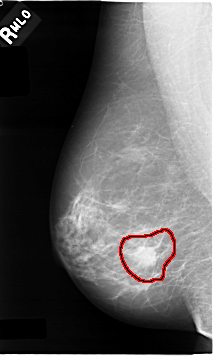

C_0009_1.RIGHT_MLO

RIGHT_MLO LINES 4640 PIXELS_PER_LINE 2768 BITS_PER_PIXEL 12 RESOLUTION 50 OVERLAY

FILE: C_0009_1.RIGHT_MLO.OVERLAY

TOTAL_ABNORMALITIES 1

ABNORMALITY 1

LESION_TYPE MASS SHAPE IRREGULAR MARGINS SPICULATED

ASSESSMENT 5

SUBTLETY 5

PATHOLOGY MALIGNANT

TOTAL_OUTLINES 1

BOUNDARY